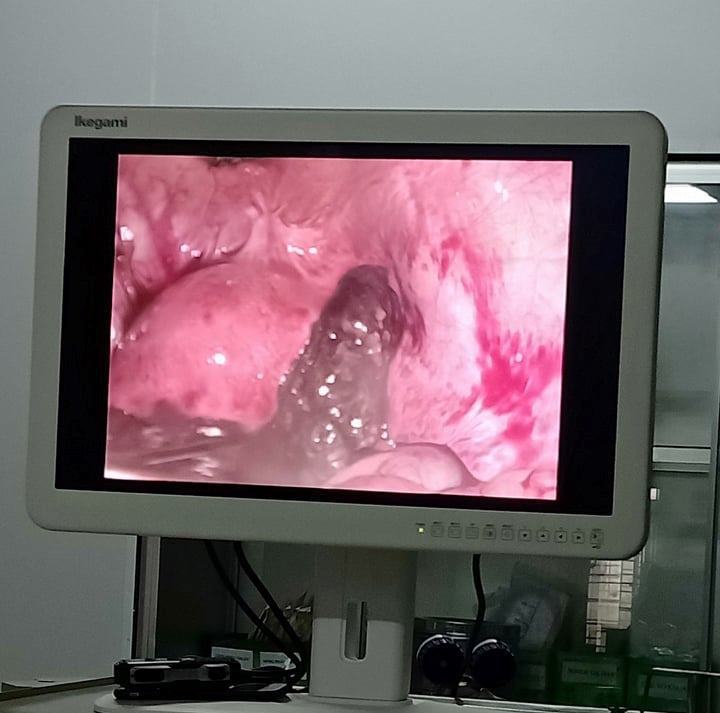

| Hình ảnh ông Thắng cung cấp cho rằng có khối thai ngoài tử cung bệnh nhân |